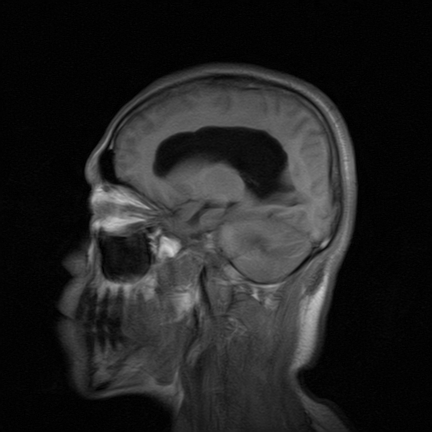

标题: MRI2064:少见病例。男性52,视力下降多年。 [打印本页]

标题: MRI2064:少见病例。男性52,视力下降多年。

四脑室区见混杂信号占位影,脑室系统扩张明显,临近结构显著受压称位,患者52岁,多考虑室管膜瘤可能性大

考虑第四脑室室管膜瘤并梗阻性脑积水;部分性空蝶鞍;左侧上颌窦粘膜下囊肿。

考虑第四脑室室管膜瘤【血供丰富血管母细胞瘤可能】并梗阻性脑积水;部分性空蝶鞍;左侧上颌窦粘膜下囊肿。

比较典型的脉络丛乳头状瘤并脑积水,鉴别小脑蚓部血管母细胞瘤。